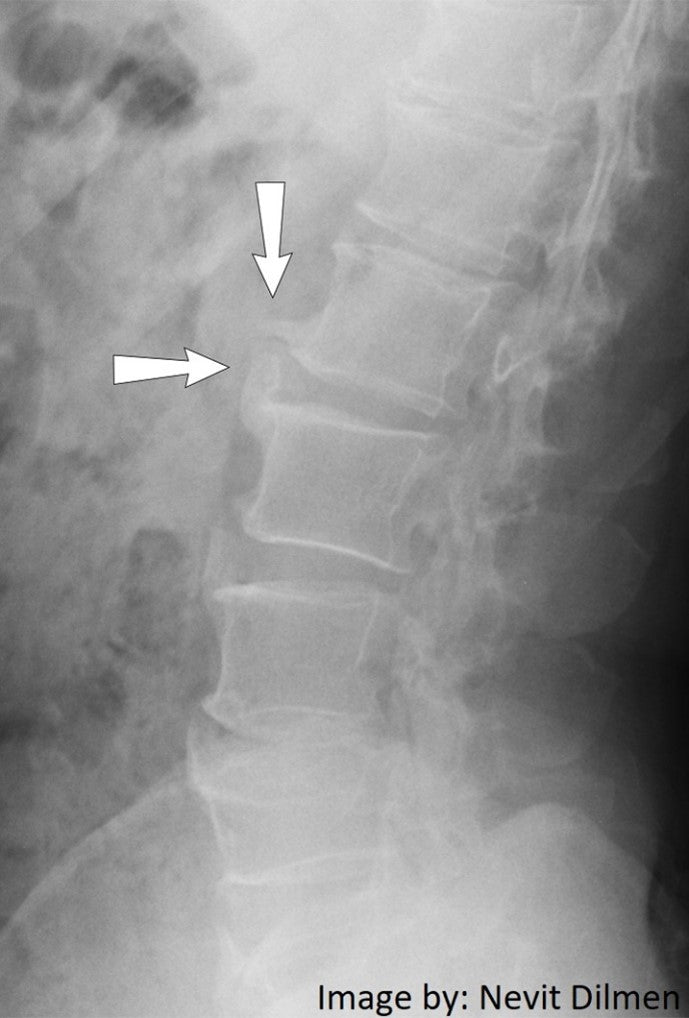

Bone Spurs aka Osteophytes:

- Are Usually Smooth in Texture

- May Not be Painful

- Commonly Caused by Osteoarthritis

- Ligaments in an aging spine can thicken and calcify, resulting in bone “spur” formation

Spinal Osteoarthritis

- Regularly occurs in spinal facet joints.

- A degenerative joint disease.

- Protective cartilage surrounding bones (providing cushioning) degenerates.

- Can cause swelling and/or pain.

- Treatment is geared toward relieving the symptoms of pain and increasing a person's ability to function.